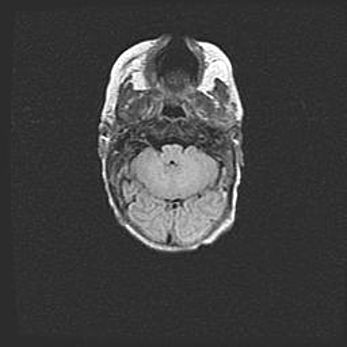

Мальформация Денди-Уокера. Киста задней черепной ямки.

Агенезия мозолистого тела.

Возраст: 2,5 месяца

Вес: 2420 г

Пол: женский

Окружность головы: 37 см

Срок гестации: 32 недели

Мальформация Денди—Уокера — редкий вид патологии ЦНС, представляющий собой врожденный порок развития каудального отдела ствола и червя мозжечка, ведущий к неполному раскрытию срединной (Мажанди) и латеральных (Лушка) апертур IV желудочка мозга. Для этогно синдрома характерна триада симптомов: гипотрофия червя мозжечка и/или полушарий мозжечка, кисты задней черепной ямки, гидроцефалия различной степени. В 70% случаев порок сочетается и с другими аномалиями головного мозга, в частности с агенезией мозолистого тела.